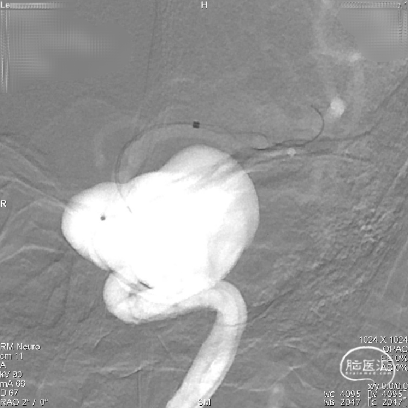

术前CT检查显示,可见左侧侧裂内侧类圆形高密度。

DSA造影显示为左侧颈内动脉海绵窦段巨大动脉瘤。

通过3D工作位测量出左侧海绵窦段动脉瘤尺寸:33mm不规则动脉瘤,载瘤动脉尺寸:近端直径4.55mm,远端直径3.97mm。

造影后发现该患者左侧海绵窦段动脉瘤,动脉瘤不规则,最大径33mm,未破裂,不累及分叉部,动脉路径迂曲。